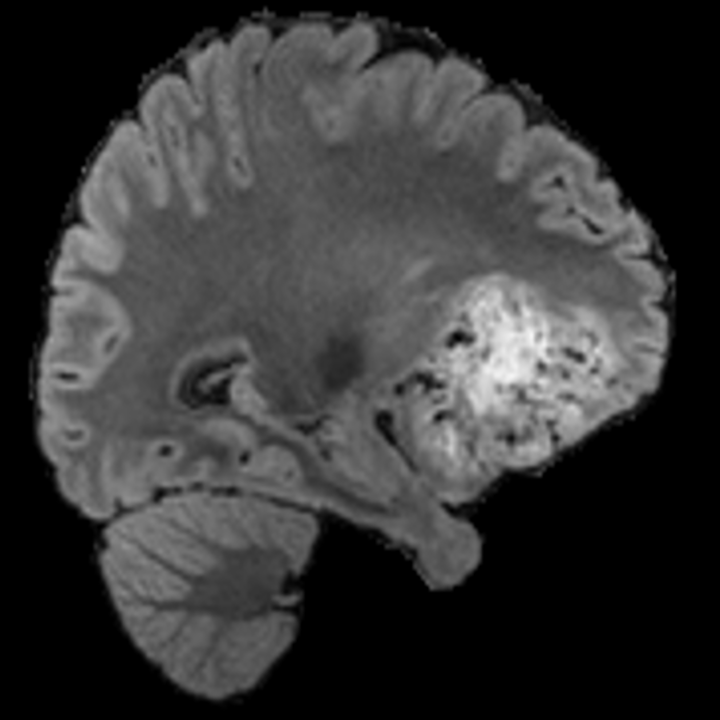

Tumour Information Preservation. For the brain tumor segmentation, we use a Swin UNETR model[28, 70], trained with random rotation, and intensity as data augmentation. On the test set with human ground-truth annotations (), the brain volumes generated from single slice input preserve the volume of the different tumour components (paired t-test, for all 3 classes). In Figure 4, we highlight the tumor profiles of the generated MRIs compared to the ground truth tumour profile. The real MRI Dice score in the test set is 85.15 while the generated MRIs from a single slice have a dice score of 83.09. This shows how the generated MRIs indeed preserve the tumor information and can act as an affordable and informative pseudo-MRI, before conducting an actual costly MRI examination in hospitals. More detailed results are provided in supplementary material.

Leveraging Context. Since we train on a predominantly cancerous brain dataset, one question that might arise is whether X-Diffusion generated MRIs preserve tumour information when the given inputs do not intersect with any tumour. We perform experiments varying the input slice index used to generate the 3D brain MRIs and measure the performance for input slices with no intersection with the tumour (not a single pixel with tumor label in the input slice). We also measure performance when only input slices are selected from tumor range. The Dice Scores of the random slices, no-tumour, and only-tumour are 83.09, 79.23, and 83.68 respectively. As can be seen here, the brain volumes generated from input slices with no tumour still preserve tumour information in reconstructed brain volumes despite a small drop in performance. This indicates that X-Diffusion is leveraging the context to preserve key information, such as tumor locations. This observation is consistent with how tumor segmentation models with global context [13] perform better than local-based U-Nets. More details are provided in supplementary material.

To see when and how X-Diffusion fails, we conducted an experiment on healthy brains (no tumour) using IXI dataset, by running an X-diffusion trained on BRATS brain tumor dataset. Our X-Diffusion achieved a PSNR of 35.86 dB on the IXI dataset despite being trained on the BRATS dataset. We then ran the tumour segmenter on the set of 582 healthy scans and corresponding generated MRIs. The segmenter predicted tumours in 9.9% of the real healthy brains and in 11.3% of the generated brain MRIs. Some of these tumor hallucination examples fron X-Diffusion generation are shown in Figure 10.